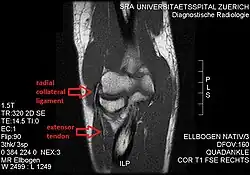

MRI of the elbow (T1 weighted) showing an unimpaired radial collateral ligament and extensor tendon.